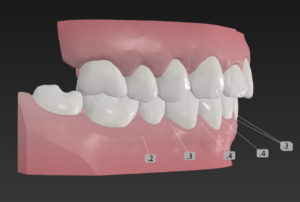

🔶矯正開始時🔶

正面

歯並びガタガタの そうせい

出っ歯さんが気になり

矯正を希望されました

今回はインビザラインでなく

クリアコレクトを選択

この歯並びが治る原理は

そうせい🟰歯と歯の間を少し削り

スキマを作って歯をキレイに整列

ただしインプラント

動かない歯とAIに指令を出すことで

矯正のプログラムをAIが考案

出っ歯🟰Ⅱ級ゴムを使うことで

上の歯列を後ろに動かす

えんしん移動で出っ歯さんを矯正